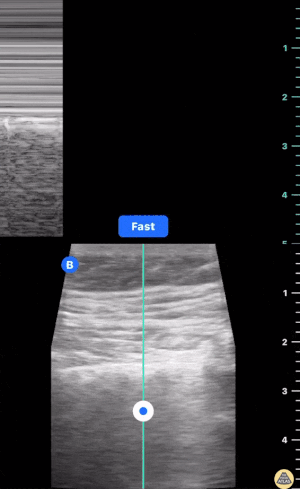

Prominent finding seen here:

Absence of lung sliding